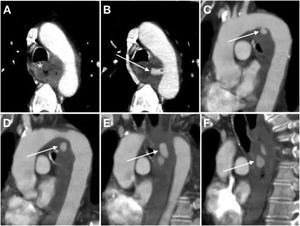

Primary aortoduodenal fistula in a 65-year-old male with an episode of intermittent vomiting and melaena for the past 2 weeks who visited the emergency department with haematemesis, dizziness and hypotension. Baseline computed tomography (A and B) demonstrated high-density (47 HU) content in the gastric chamber in relation to a clot and a calcified aneurysm in the abdominal aorta with an intramural haematoma. The arterial phase (C) revealed a saccular bulge on the anterolateral aspect of the aorta with loss of the fat plane achieving separation with the duodenum (*). The late phase (D) did not demonstrate clear extravasation of IVC. Laparoscopy confirmed the presence of an AEF (E) (a: aorta; d: duodenum; f: fistula) which was repaired in the same surgical procedure (F) including segmental resection of the duodenum.